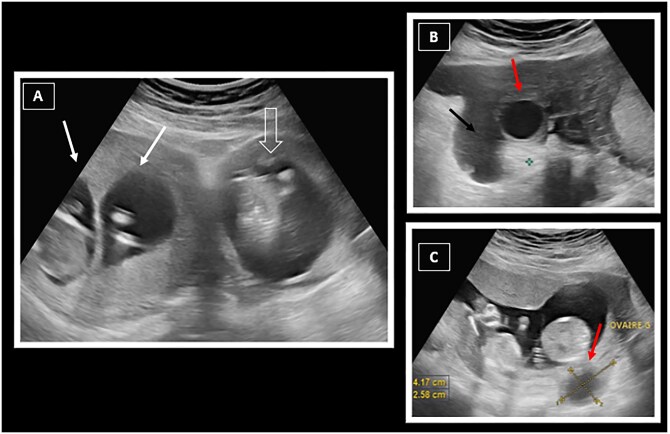

Heterotopic pregnancy refers to the concomitant presence of an intrauterine pregnancy and an ectopic pregnancy (EP). It is rare and more frequently found in women who have undergone medically assisted procreation. An abdominal location of the ectopic gestational sac is even less common, accounting for 1.4% of all ectopic pregnancies, conferring a high risk of morbidity and mortality. Diagnosis can sometimes be difficult, and pelvic ultrasound alone may not be sufficient. Additional pelvic MRI may be useful to confirm the diagnosis with certainty. Heterotopic pregnancy requires urgent management and is mainly treated surgically, although there are certain situations where medical treatment may be indicated. We report the case of a 29-year-old patient admitted with pelvic pain and mild metrorrhagia, with an elevated beta-hCG level suggesting the diagnosis of an EP, which was confirmed by ultrasound and MRI, revealing the presence of 3 foetuses: 1 was developing in the abdominal cavity while the other 2 were normally present in the uterine cavity.